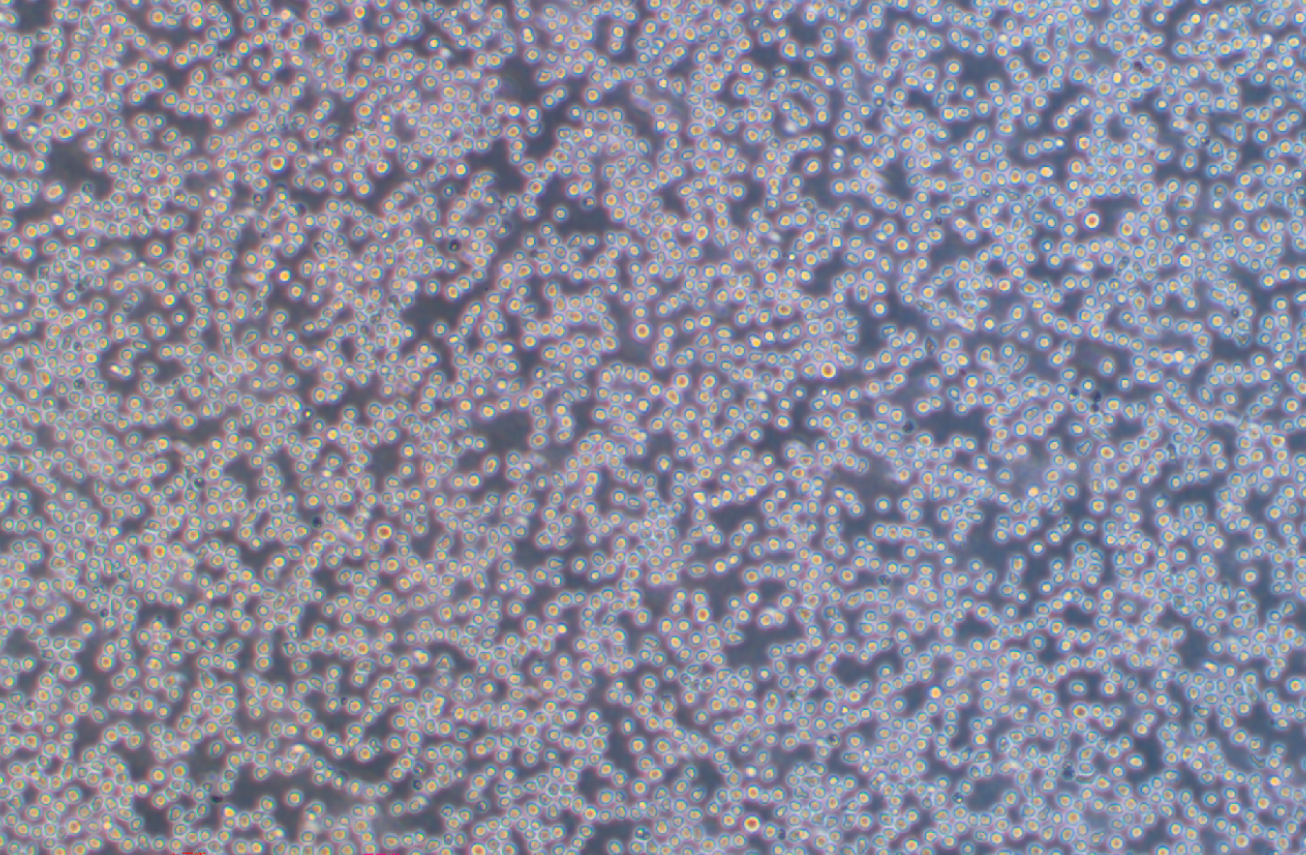

形態 |

淋巴母細胞樣 |

生長特征 |

懸浮生長 |